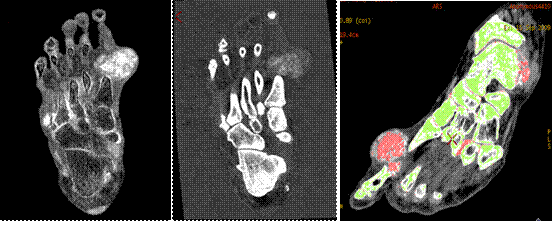

新技術(shù)介紹三:物質(zhì)分離與定量

MD尿酸像 MD鈣基像 尿酸與骨質(zhì)分離

痛風(fēng)由于尿酸結(jié)晶體沉積在人體組織所致,而假性痛風(fēng)是由于磷酸鈣鹽沉積所致。如果在關(guān)節(jié)內(nèi)不進行穿刺活檢無法評估尿酸結(jié)晶存在。寶石能譜CT物質(zhì)分離像可以提示痛風(fēng)或者假性痛風(fēng)存在,并加以鑒別。